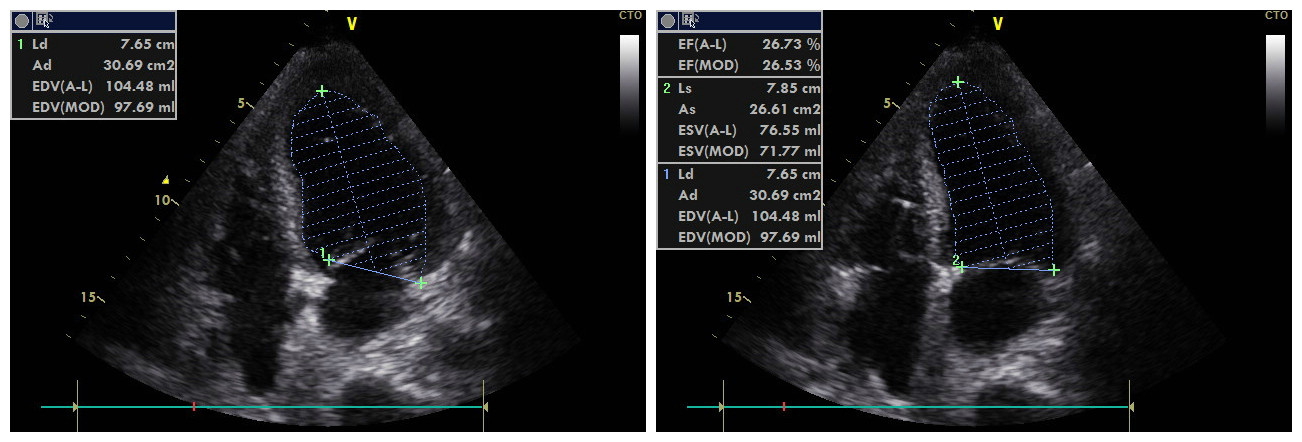

1.2 研究方法所有患者在入住重症监护病房后均予记录一般资料,包括:年龄、性别、心电图是否存在ST段弓背向上抬高、是否行急诊经皮冠状动脉介入术、是否需要有创机械通气、基础病(高血压、糖尿病、慢性肾脏病、肺部感染)、序贯器官衰竭估计评分(sequential organ failure assessment, SOFA)、急性生理与慢性健康评分(acute physiology and chronic health evaluation, APACHE)Ⅱ、白细胞计数、血小板计数、白蛋白、总胆红素、血肌酐、降钙素原。并根据急性心肌梗死相关指南[8-9]给予治疗。所有患者在入住重症监护病房时均予锁骨下静脉穿刺或颈内静脉穿刺置入中心静脉导管(国械注准20153031562,广东百合医疗科技股份有限公司,中国),并经床旁胸片确定中心静脉导管位置位于上腔静脉。在对侧手臂予以动脉穿刺置入一次性使用动脉导管[国食药监械(进)字2011第3152874号,中国]。经中心静脉置管留取静脉血,同时经对侧动脉置管留取动脉血。对静脉血和动脉血应用血气分析仪(ABL90,雷度米特,丹麦)行血气分析。通过静脉和动脉血气结果计算Pcv-aCO2,同时记录静息心率、平均动脉压(mean arterial pressure, MAP)、中心静脉压(central venous pressure, CVP)、中心静脉血氧饱和度(central venous oxygen saturation, ScvO2)、动脉血乳酸(lactate, Lac)。6 h后由专业的超声科医生应用超声诊断仪(VIVID Q,通用电气,美国)行经胸壁二维超声心动图检查。应用二维双平面改良Simpson法则计算LVEF。二维双平面改良Simpson法则:在心尖四腔上选取左心室面积最大的切面测量左心室容积。由舒张末期容积和收缩末期容积的测量值计算LVEF,计算公式为LVEF =(舒张末期容积-收缩末期容积)/舒张末期容积×100%[5]。见图 1。在患者转出重症监护病房时记录在重症监护病房监护期间的肌钙蛋白I峰值。

| 图 1 二维双平面改良Simpson法则示例 Fig 1 Example of the two-dimensional biplane modified Simpson' s law |